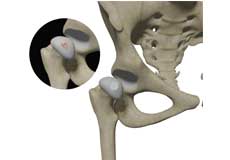

Avulsion Fractures of the Pelvis

Avulsion fractures of the pelvis is an injury that occurs when a tendon or ligament pulls off a piece of bone from the hip.